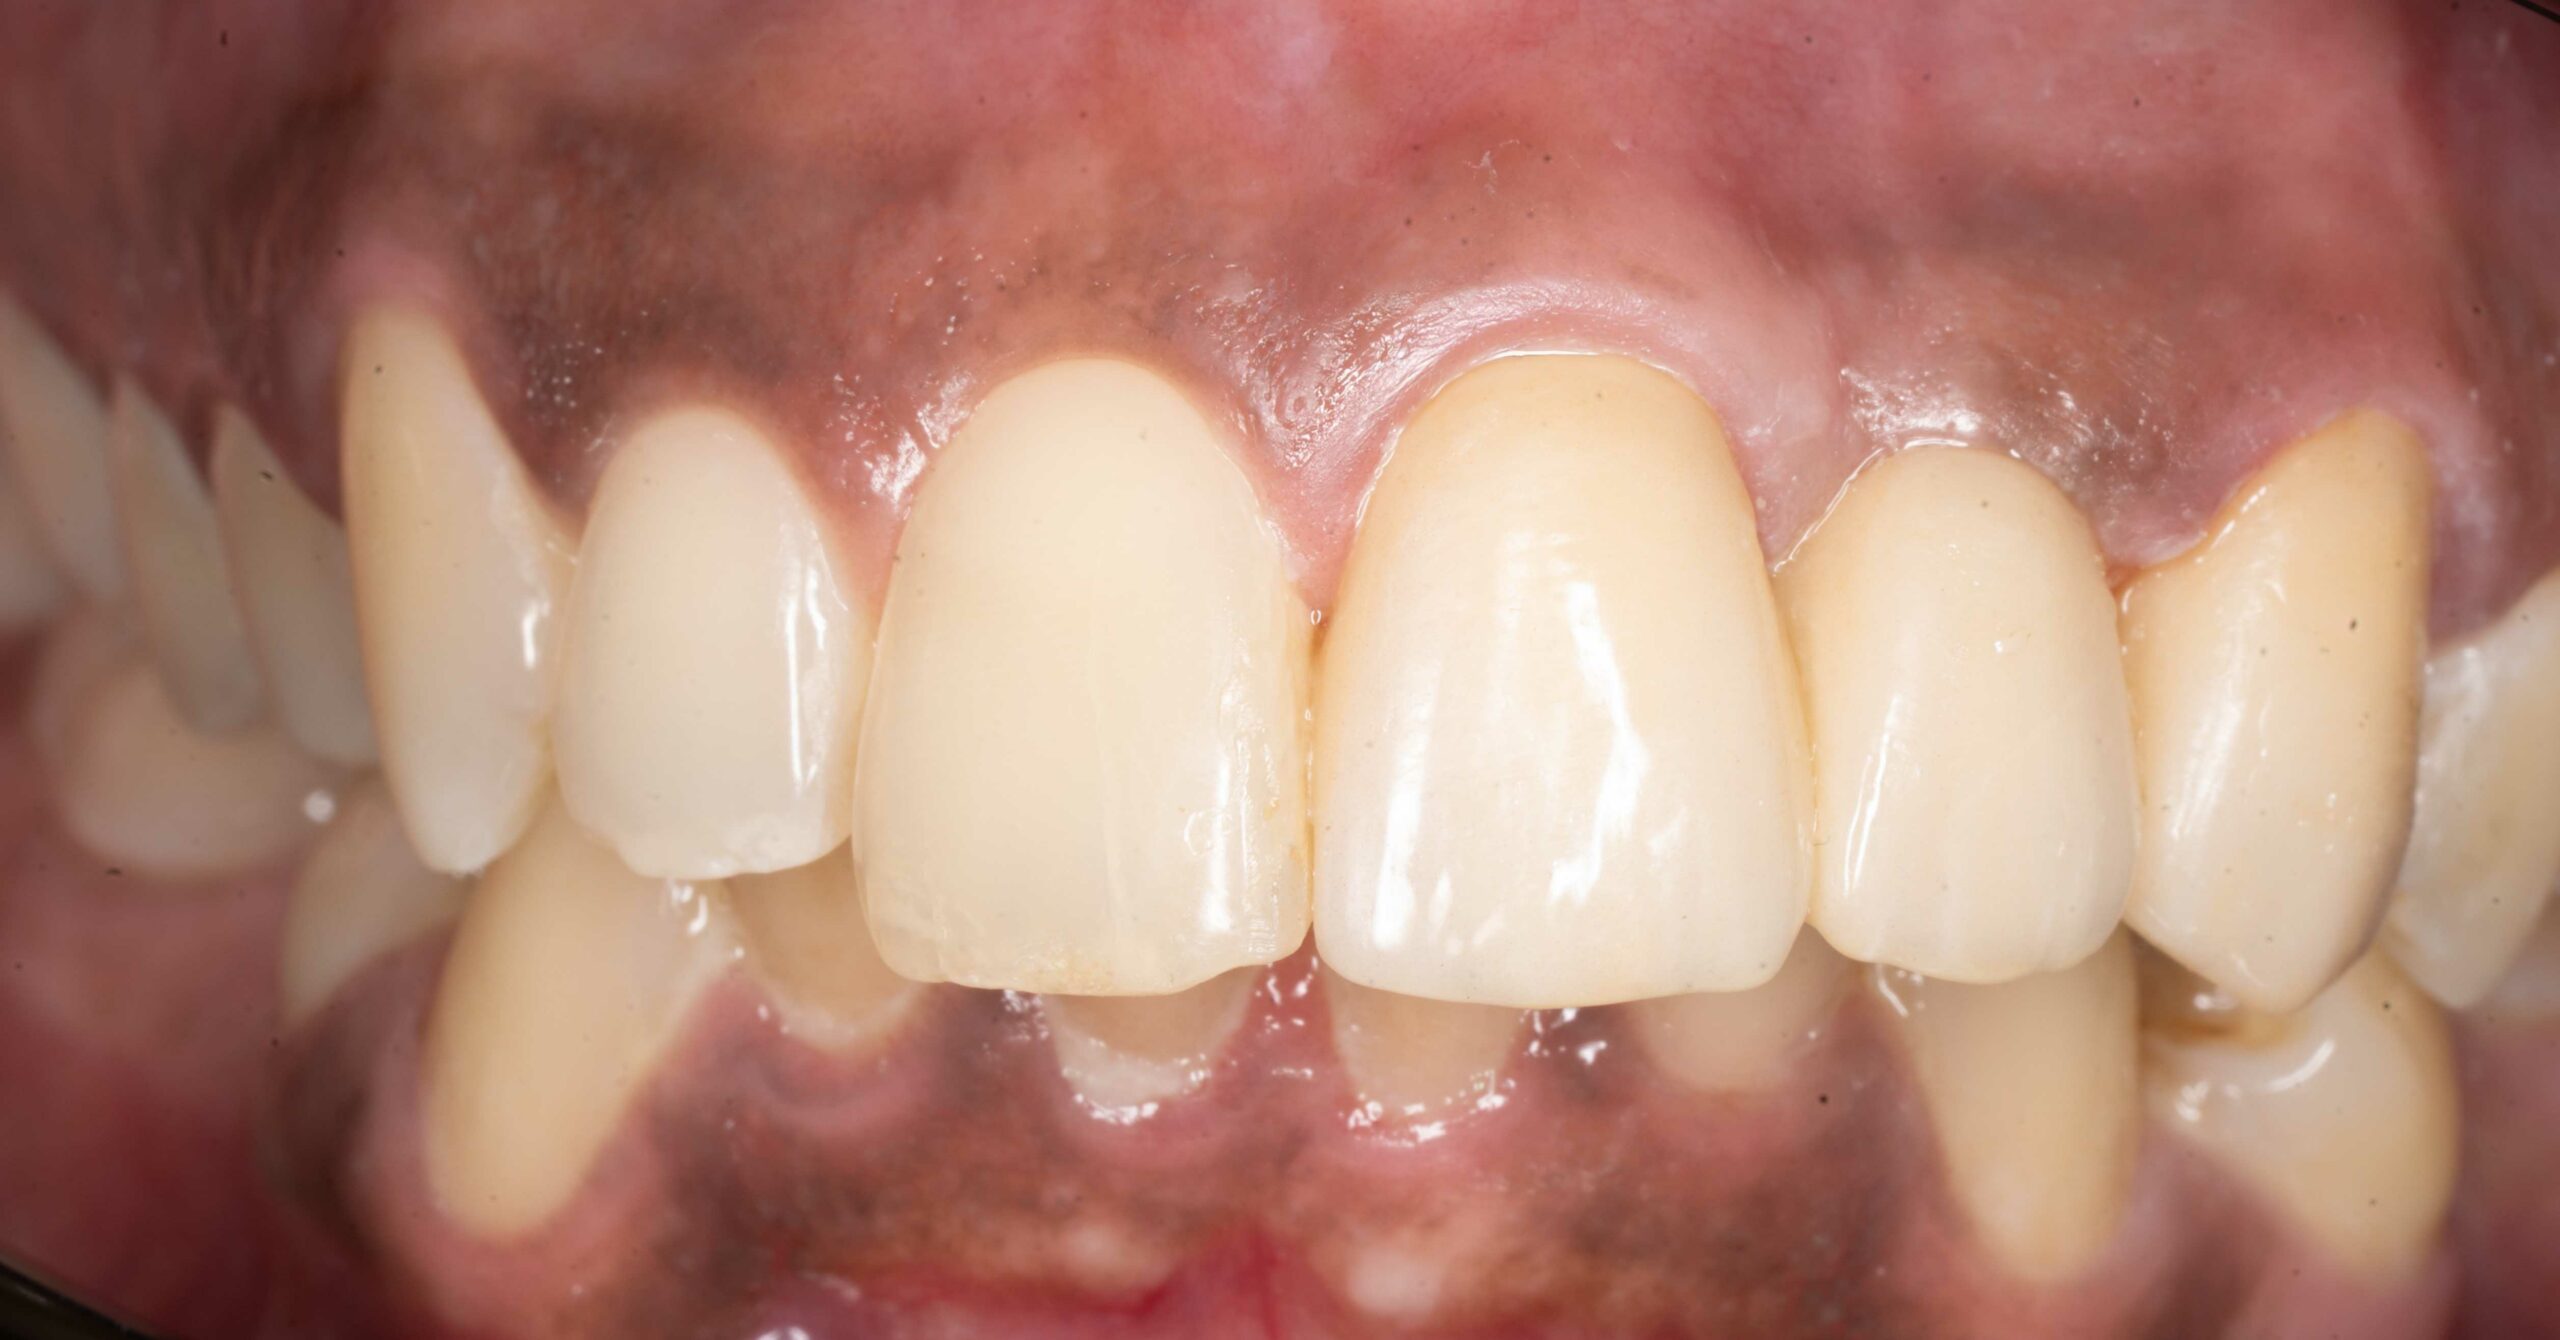

utrata zęba po urazie

Nasi pacjenci mogą liczyć na niezwłoczną oraz profesjonalna pomoc w każdej, nawet najbardziej stresującej sytuacji. Młoda pacjentka zgłosiła się z powodu utraty zębów przednich, do czego doszło kilka dni wcześnej, w wyniku potracenia przez kierowce elektrycznej hulajnogi. Leczenie polegato na niezwtocznym wprowadzeniu implantów zebowych oraz tymczasowej odbudowie zebów, dzieki czemu pacjentka jeszcze tego samego dnia odzyskata peten usmiech. Wprowadzenie implantów w odcinku przednim stanowi niezwykte wyzwanie. Aby osiagnac naturalny wyglad oraz wysoka estetyke czesto wymaga dodatkowych zabiegów regeneracyjnych na okolicznych tkankach miekkich oraz twardych. Przedstawiony efekt to uśmiech po wykonaniu ostatecznej odbudowy protetycznej.